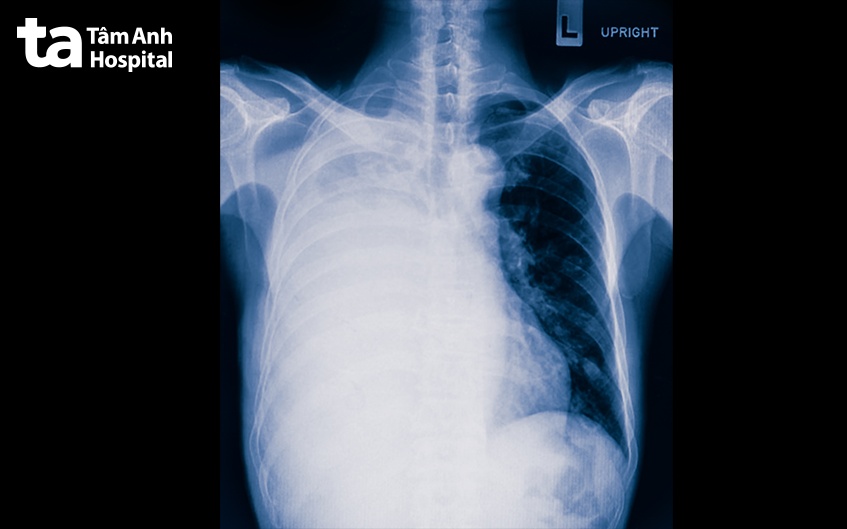

Hình ảnh X-quang xơ phổi đóng vai trò quan trọng trong việc chẩn đoán bệnh xơ phổi. Thông qua kết quả hình ảnh, bác sĩ có thể nhận biết và đánh giá những tổn thương ở phổi, đặc biệt là hình ảnh tổn thương xơ (dấu hiệu điển hình của bệnh xơ phổi).

Bệnh xơ phổi thường xuất hiện trên phim X-quang là hình mờ dạng lưới ở ngoại vi phổi, rõ hơn về phía đáy phổi, có thể khiến bờ tim trở nên không rõ, gồ ghề. Dấu hiệu bệnh xơ phổi còn thể hiện trên phim Xquang là các nang nhỏ hình dạng giống như tổ ong. Giai đoạn tiến triển, tổn thương trở nên lan tỏa và gây giảm thể tích phổi.

Quá trình đọc kết quả hình ảnh X-quang xơ phổi có chính xác hay không còn phụ thuộc vào chất lượng của hình ảnh. Kinh nghiệm, trình độ chuyên môn của bác sĩ chẩn đoán hình ảnh và bác sĩ chuyên khoa hô hấp cũng góp phần quan trọng.